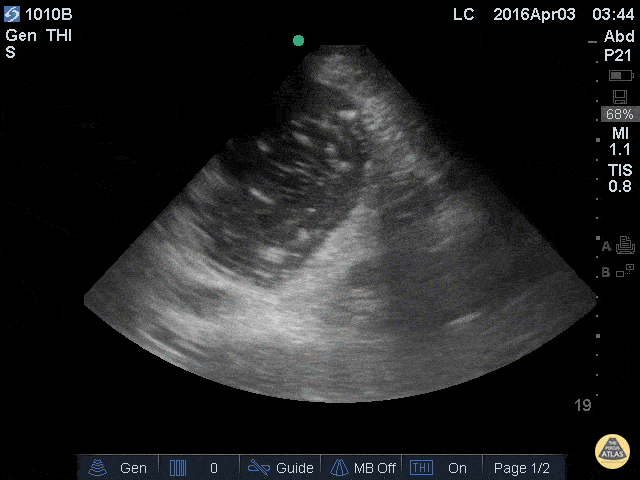

A 76 y/o F ward patient was vomiting and in respiratory distress possibly due to aspiration. The patient had impending respiratory failure and the plan was to intubate and admit to ICU. A POCUS was done to evaluate her distended abdomen prior to intubation and the image demonstrated a grossly distended stomach with swirling hyperechoic particles. NG tube was placed and approximately 1 liter of bilious fluid was removed. Patient was safely intubated thereafter with aspiration risk minimized. Learning point: For peri-intubation patient with high aspiration risk, POCUS can help determine the amount of gastric content and potentially alter management to include maneuvers to minimize aspiration risk. Van de Putte P, Perlas A. Ultrasound assessment of gastric content and volume. Br J Anaesth. 2014 Jul;113(1):12-22. doi: 10.1093/bja/aeu151. Submitted by Leon Chen, NP – Critical Care Medicine Service Department of Anesthesiology and Critical Care Medicine Memorial Sloan Kettering Cancer Center - New York, NY